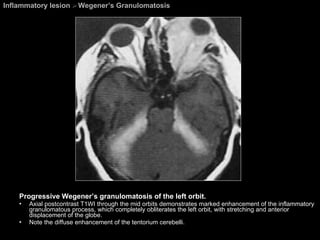

Inflammatory lesion  >  Wegener’s Granulomatosis Progressive Wegener’s granulomatosis of the left orbit. Axial postcontrast T1WI through the mid orbits demonstrates marked enhancement of the inflammatory granulomatous process, which completely obliterates the left orbit, with stretching and anterior displacement of the globe.  Note the diffuse enhancement of the tentorium cerebelli.

Wegener’s Granulomatosis A multisystem disease. Mainly occurs in the fifth decade of life.  A triad: Necrotizing granulomas in the upper and lower respiratory tracts Necrotizing vasculitis of the lung, upper respiratory tract, and other sites. Glomerulonephritis. If left untreated, the disease is often fatal.  Combined corticosteroid cyclophosphamide treatment has proven very successful.

Wegener’s Granulomatosis Ocular involvement is also common: occurring in 18% to 50% of the cases. The disease  most commonly spreads from the paranasal sinuses to the orbit . The CT and MR imaging appearance ; Similar to that of  pseudotumor  and  lymphoma. Nasal and paranasal sinus involvement  is present in the majority of cases.